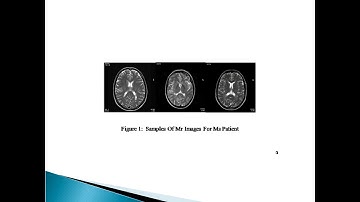

An Improved Fuzzy C Means Algorithm for Brain MRI Image Segmentation in Matlab